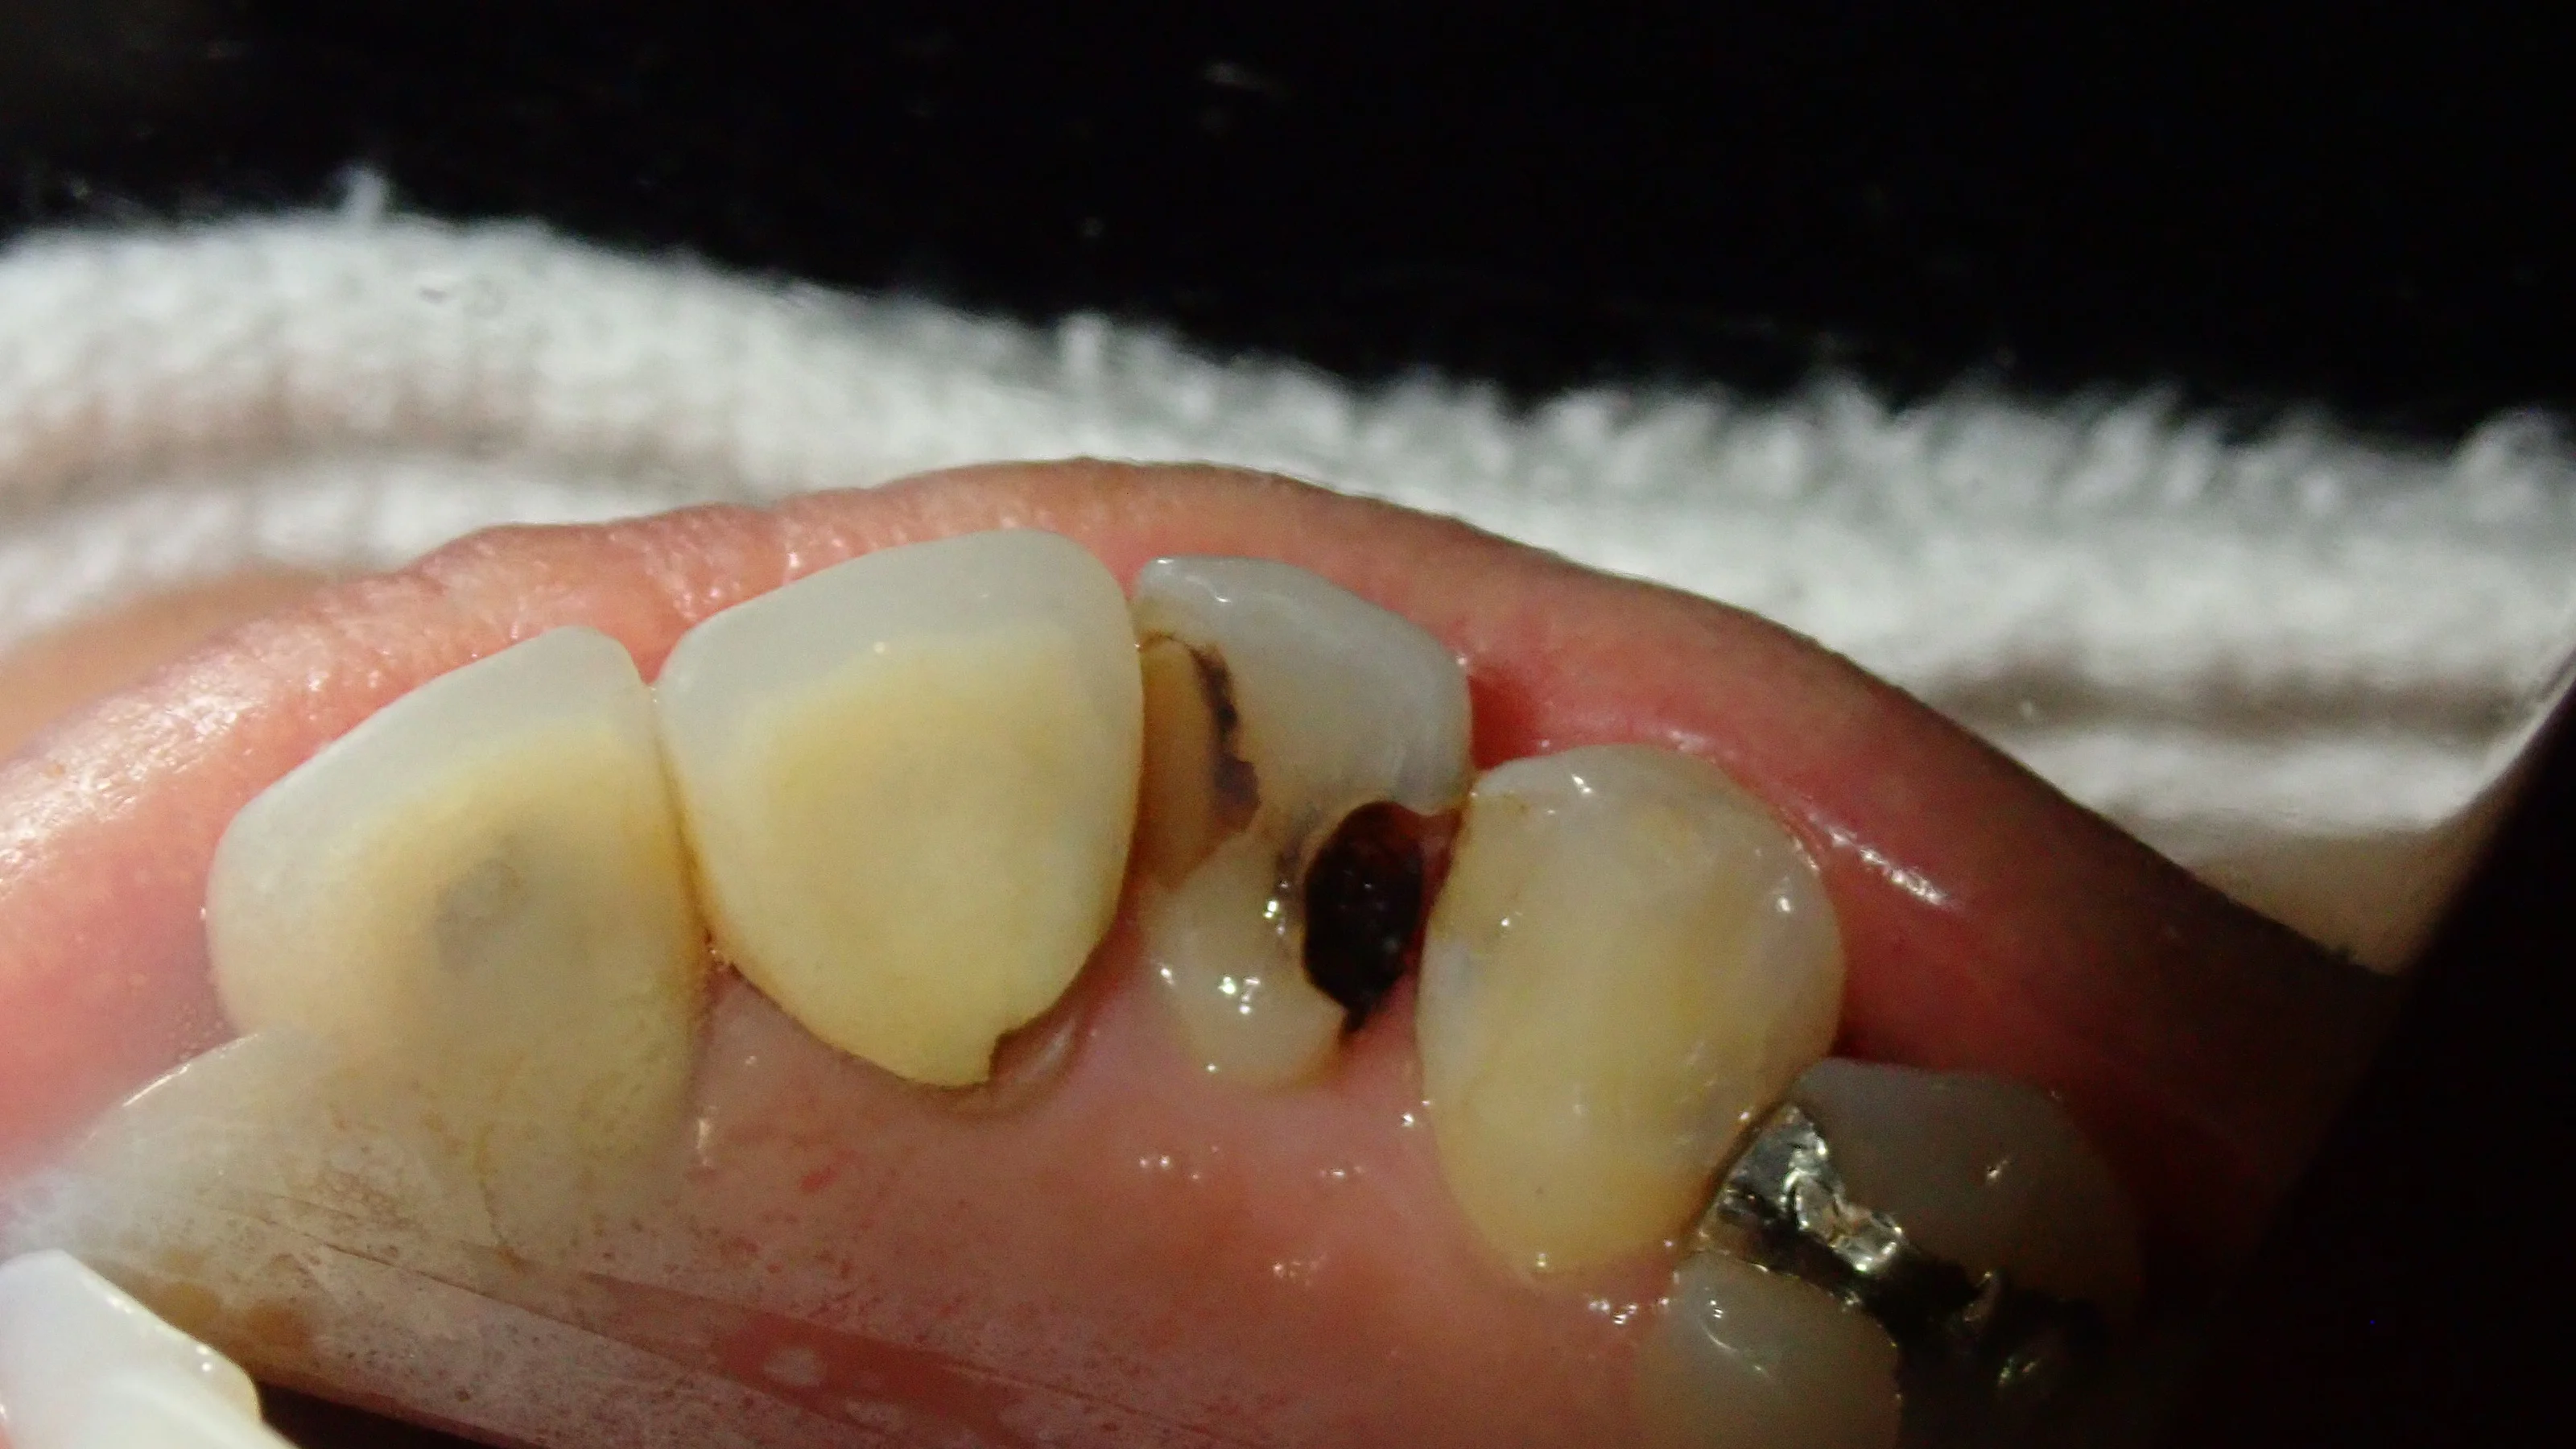

まずは術前の状態です。

歯の表側から見た状態です。

どこが虫歯か分かりますかね?

今回は結構色が透けているので、なんとなく虫歯になってるっぽいなと一般の方でも分かるかと思いますが・・・

裏側から見るとこんな状態になってしまっていました。

前後の歯の間から虫歯が入り込み、歯の中央で虫歯が繋がっている状態となっています。

歯科医師によってはいきなり抜髄処置に入ってもおかしくはないほどの虫歯です。